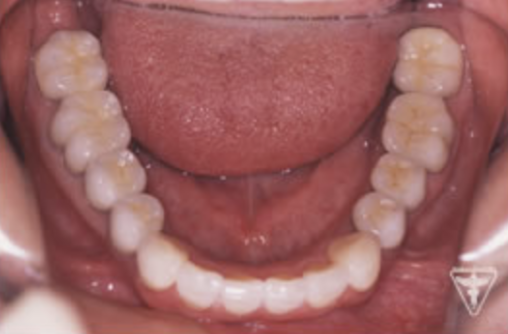

初診時の正面観・側方観・かみ合わせの面の状態を示します。

下の顎のずれがあるのを確認して下さい。

治療後

初期治療を経て歯周外科、歯内療法により病巣の消失が認められ改善された。

咬んだ感じが軽くなり、よく咬めると評価を頂きました。